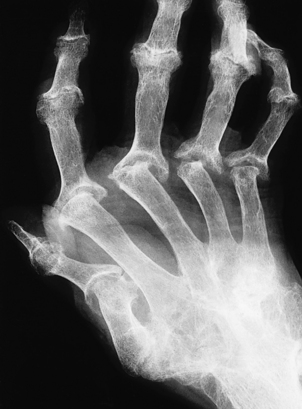

Osteoporosis often develops in the bones immediately adjacent to affected joints, particularly in the fingers. This is often the first radiological change of rheumatoid disease, but small pocket-like erosions of the peri-articular surface are also seen (Fig. 25.20). In chronically diseased joints the articular cartilage is extensively eroded and fragmented and the resultant debris is a further source of synovial inflammation. The loss of articular cartilage, along with damage to the joint capsule and peri-articular structures, causes deformities (Fig. 25.20) and secondary osteoarthritis can develop, particularly in the knee.

image

Fig. 25.20 Radiological features of rheumatoid arthritis. There is prominent ulnar deviation in longstanding rheumatoid disease. There are erosions of the distal metacarpal bones and of most of the carpal bones.